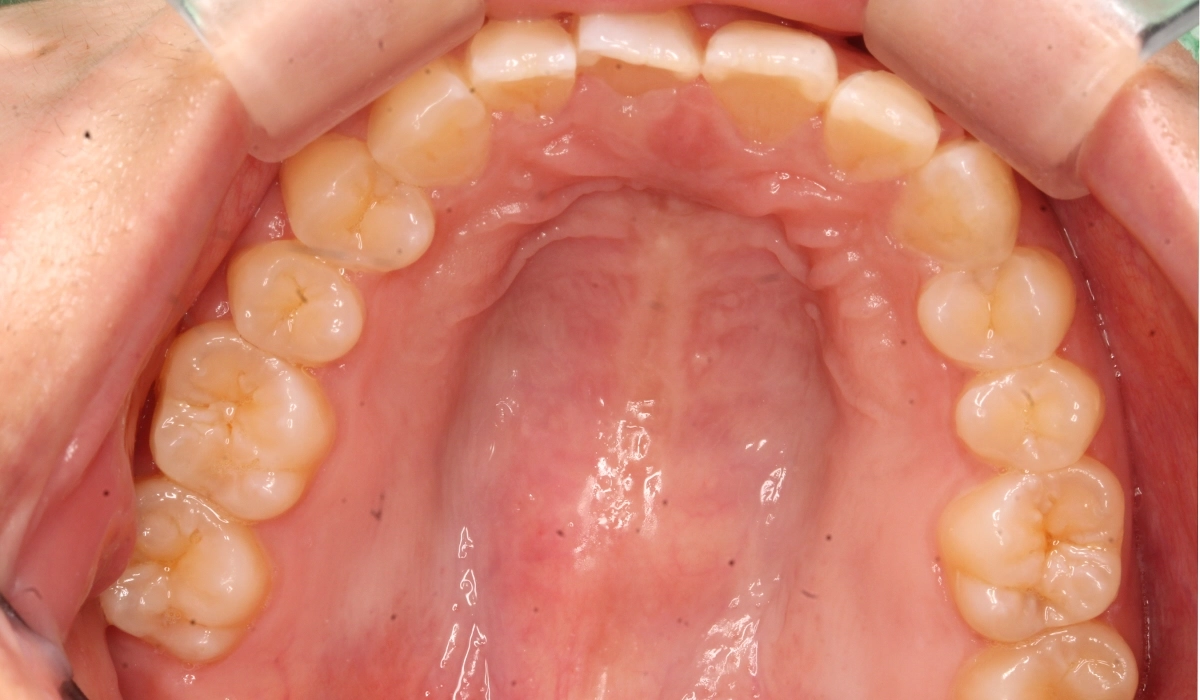

術前:下顎

術後:下顎